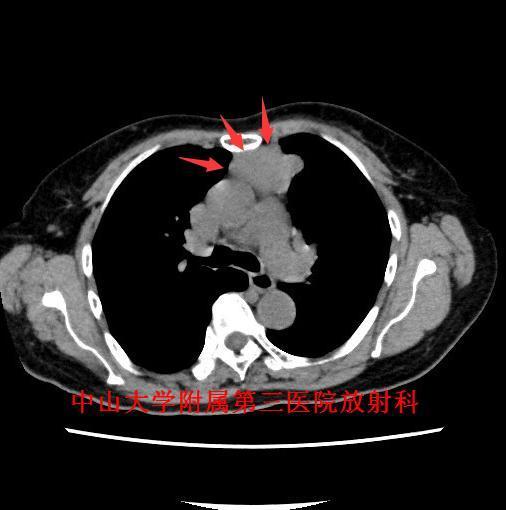

主诉:咳嗽咳痰1月余,发现前纵隔肿物4天。 病史:老年女性,慢性病程。患者于1月余前出现反复咳嗽,咳痰,无痰中带血及咯血,遂至我院门诊就诊,行胸片及胸部CT检查提示“前纵隔肿物,胸腺瘤?”。

查体:胸廓对称无畸形,无挤压痛,呼吸运动度及语颤对称,双肺叩诊清音,呼吸音清晰。 辅查:胸部CT示:前纵隔肿物,胸腺瘤?

诊断:胸腺瘤。 治疗:排除手术禁忌症,于全麻下行“正中开胸胸腺扩大切除术”,病理提示:(胸腺肿物)符合胸腺瘤(AB型);免疫组化结果(②):CK(+),Vim(部分+),EMA(-),CK7(+),CK19(+),CK20(-),TdT(-),CD5(淋巴细胞+),CD1α(淋巴细胞+),Ki-67(淋巴细胞约60%+)。

讨论:胸腺瘤是前纵隔最常见的肿瘤,约占成人前纵隔肿瘤的50%。目前,CT是公认的早期检出及诊断胸腺瘤的最佳方法。CT一般表现为:圆形、卵圆形或分叶状肿块,边界清晰,多数密度均匀,可见钙化;大部分肿瘤生长不对称,居于前纵隔的一侧;直径<2cm的胸腺瘤可仅表现为正常胸腺边缘局部隆起;增强扫描仅有轻度强化。主要应与胸腺增生鉴别,后者胸腺体积弥漫性增大,以左右两叶增厚为主要特征,但仍保持正常形态,而胸腺瘤为局部结节。 参考文献:杨蕊梦,许乙凯,冯婕等.胸腺瘤的MSCT-病理-临床综合诊断[J].放射学实践,2007,22(7):711-713.